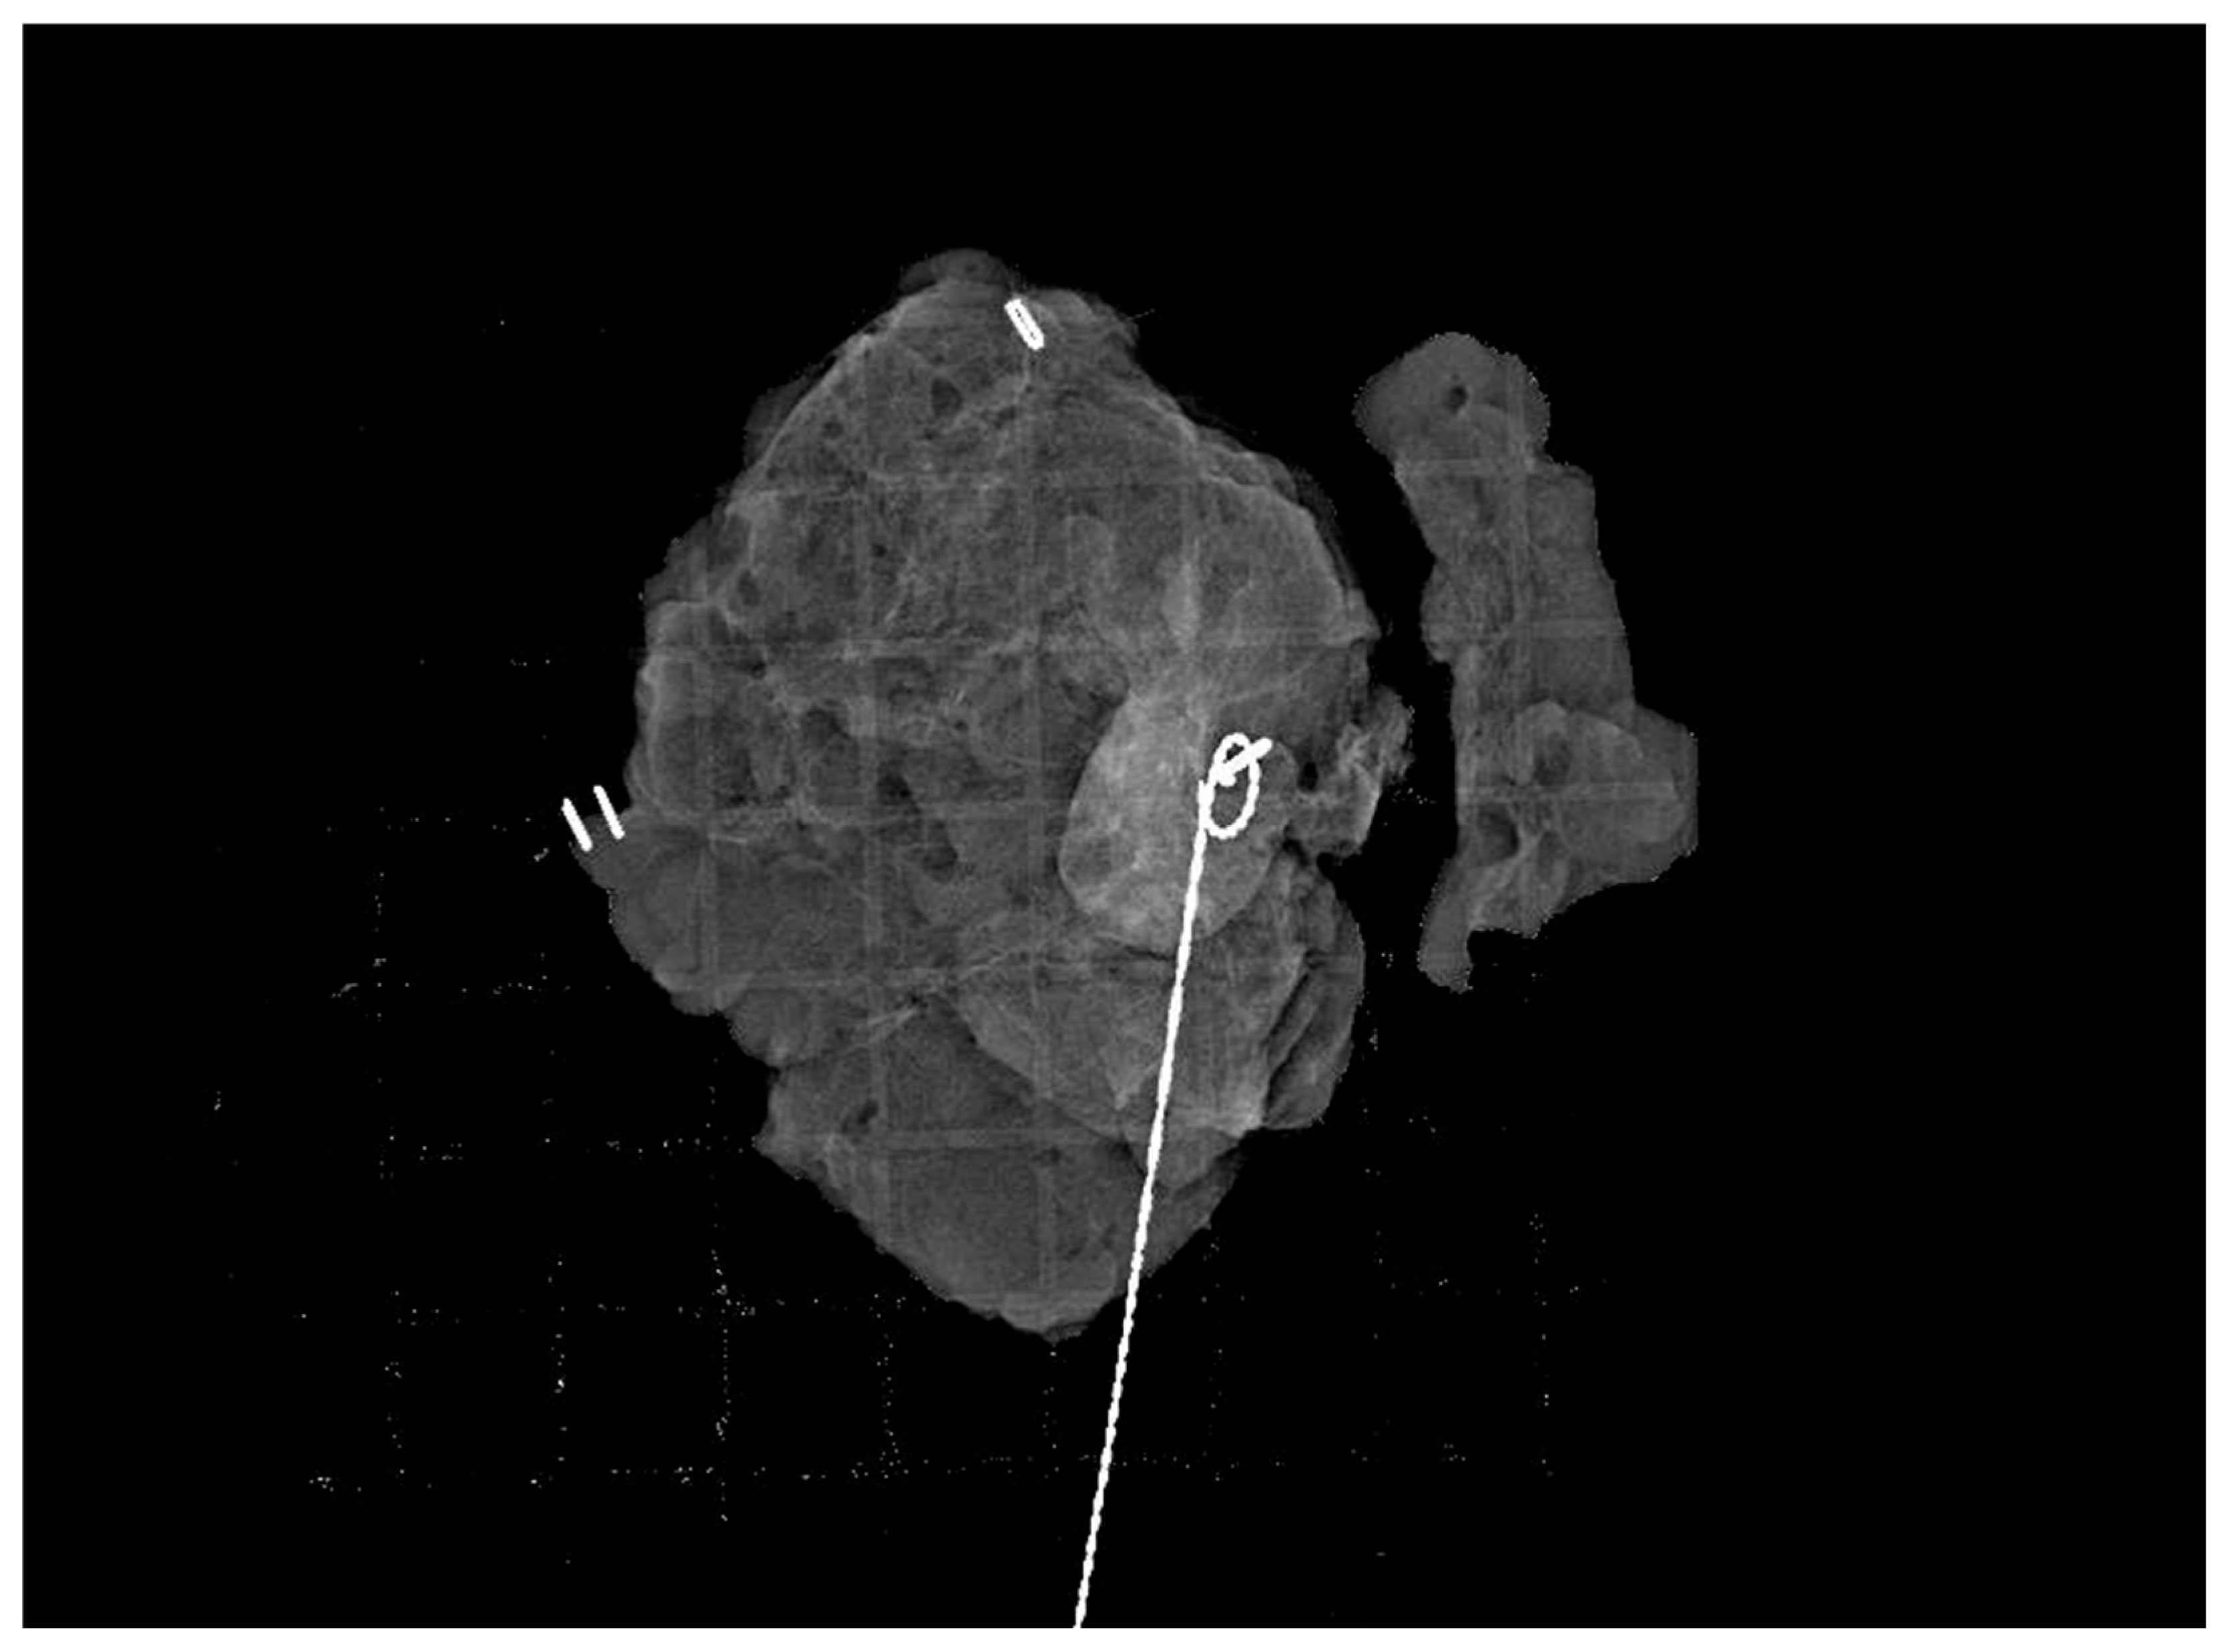

2.4. Study Variables and Procedures